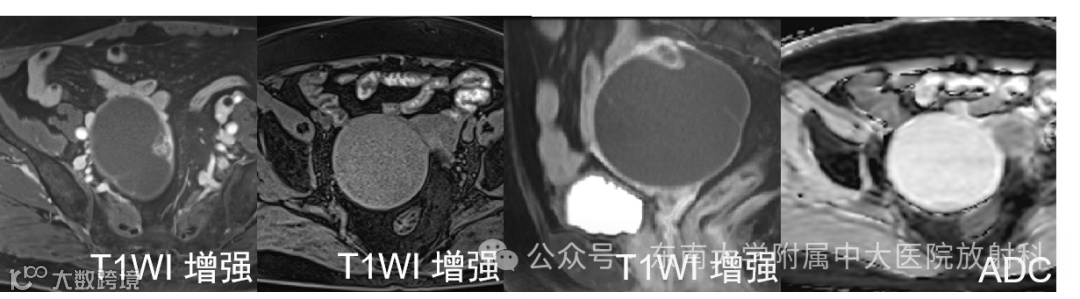

女 ,69岁 主诉:发现盆腔包块 1 天

现病史:患者53岁自然绝经,无异常阴道流血、流液。1 天前于我院体检发现盆腔包块,查阴道B超:右侧附件区见一囊性包块,大小:8.2cm×6.7cm×7.6cm,外形尚规则,界尚清,壁厚 0.24cm,内部透声差,见散在小颗粒样中高回声,见数条分隔带,CDFI:囊壁上见少量血流信号

有尿频尿急,无腹痛腹胀,无腰酸。实验室检查无异常